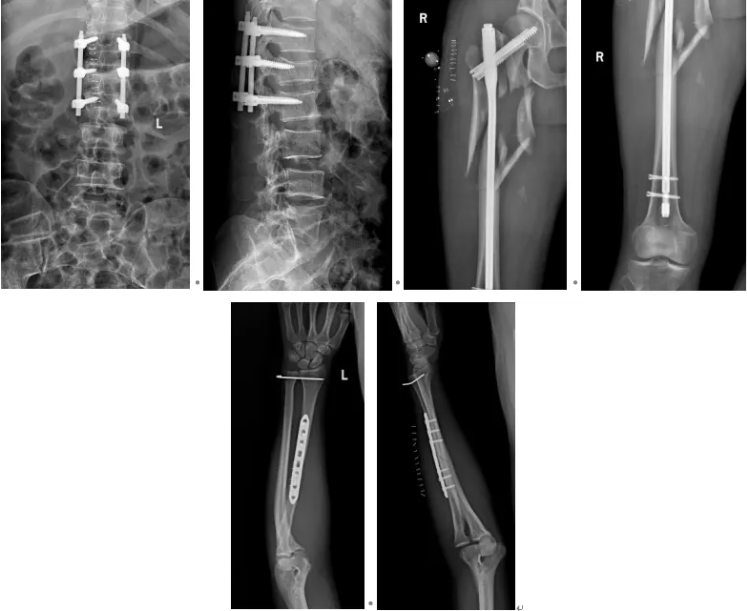

6月9日,为患者实施右股骨、左桡骨、腰 1 椎体爆裂性骨折复位内固定术,同时对左股骨远端开放性骨折再次清创,确认伤口无感染迹象,基底长出新鲜肉芽组织;

6月20日,左股骨远端开放性骨折创面血运良好,顺利完成皮肤缝合;

8月7日,动态监测显示患者各项炎症指标逐步下降,多次分泌物培养均无细菌生长,床旁拆除外固定架,改用左下肢支具保护;

8月26日,实施开放性左股骨远端粉碎性骨折坏死组织切除性清创术,取出原有内固定物,采用万古霉素抗生素骨水泥钢板内固定术,彻底稳固骨折部位。

术后,为患者提供镇痛、消肿、预防感染及下肢深静脉血栓等综合治疗,并指导其开展左膝关节屈伸功能锻炼。经过近3个月的系统救治与康复,患者各切口愈合良好,肢体功能基本恢复,顺利达到出院标准。